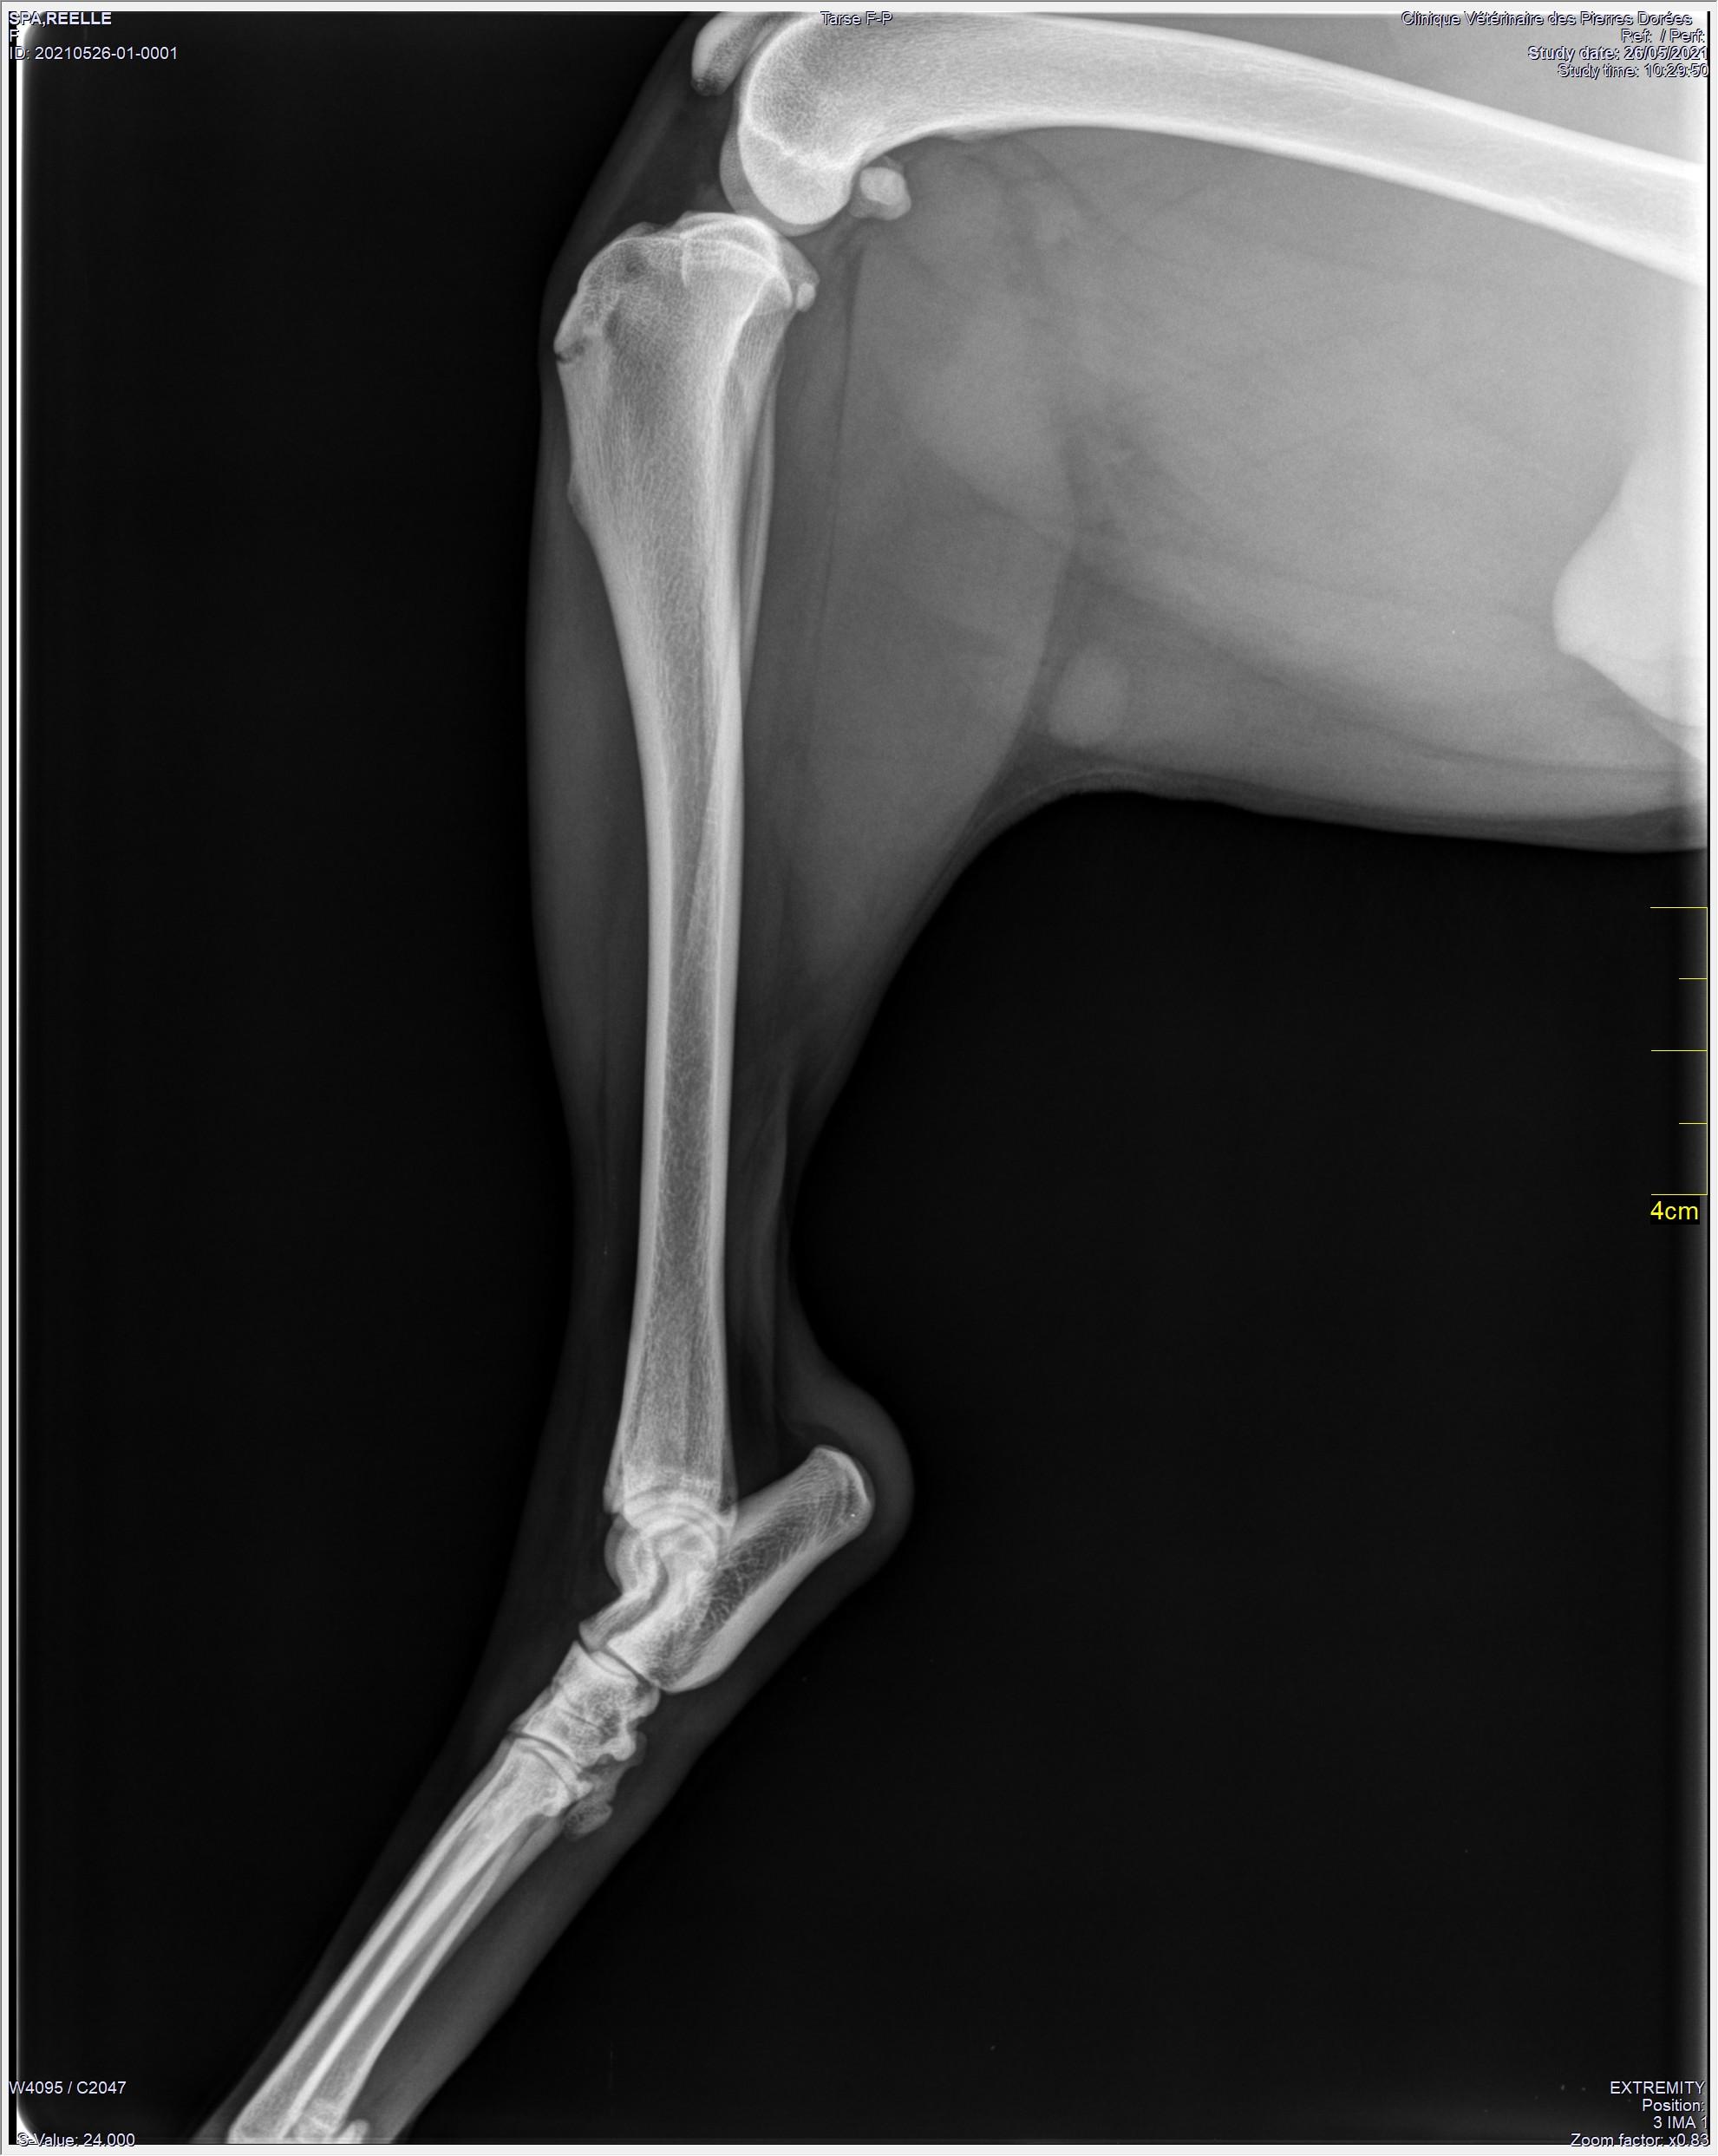

Réelle est une martyre de la Guadeloupe. Elle a été torturée, brûlée avec des cigarettes et attaquée à coups de machette. Cette pauvre louloutte errait dans la rue, sanguinolante, lorsque les fées l'ont trouvée, elle souffrait de ses plaies ouvertes et profondes mais aussi une de ses pattes arrière a reçu un coup de machette brisant le tibia et sectionnant une de ses articulations. Oui c'est terrible ce qu'a vécu Réelle et c'est à se demander si c'est possible. Sa bonne fée l'a donc appelée Réelle et a soigné ses plaies. Réelle va devoir être opérée car ça n'a pas pu être fait en Guadeloupe. Incroyable mais vrai, Réelle malgré toute cette cruauté faite par des humains, recherche leur compagnie .. Elle a besoin de l'humain, l'aime et aura besoin d'une famille présente. Jeune elle adore courir (même sur 3 pattes), donc une famille présente, aimante et sportive. Elle est en famille d'accueil dans le sud de la France avec chats et chiens. Pour le moment elle ne peut pas être adoptée, elle va être opérée. Nous avons besoin de marraines, parrains pour nous aider à financer cette opération. Si son histoire vous touche et que vous voulez participer à son sauvetage alors aidez-la, aidez nous en mettant en place un parrainage qui nous permettra de continuer à sauver ces chiens martyrs venus de Guadeloupe ou de la Réunion, ou faites un don sur le lien suivant : nous soutenir . Merci pour elle, merci pour ces loulous si gentils malgré tout le mal qui leur est fait. Pour plus d'infos contact fanny : 06 48 56 74 56 merci à tous.